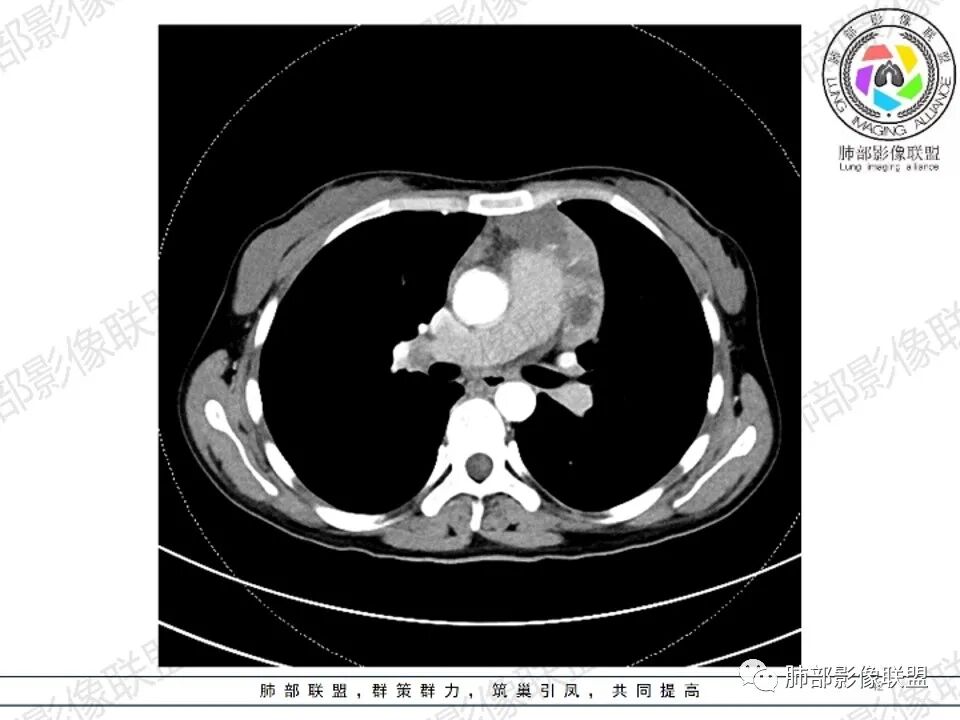

女,27,间断头晕、乏力3年,左眼视物模糊2月。贫血。胸部CT:前纵隔不规则肿块,多结节融合,边界不清,沿主动脉及肺动脉间隙生长,平扫密度欠均匀,增强扫描可见多发低密度坏死,纵隔血管供血穿行,腋窝多发大小不等淋巴结肿大。考虑恶性病变,胸腺癌?肉瘤?淋巴瘤?鉴别胸腺瘤、结节病等。

2.影像显示前纵隔不规则块状影,依势贴附心脏大血管旁,密度不均,边界不甚清楚,有结节融合感。

3.病灶轻度不均匀强化,可见血管穿行,散在液性低密度区。

双肺门未见肿大淋巴结。

4.双侧腋窝区见增大淋巴结,边界清楚。

1.年轻女性,前纵隔不规则块状影,密度不均,边界不甚清楚,有结节融合感,轻度不均匀强化,可见血管穿行,最常见最符合的无疑是淋巴瘤!